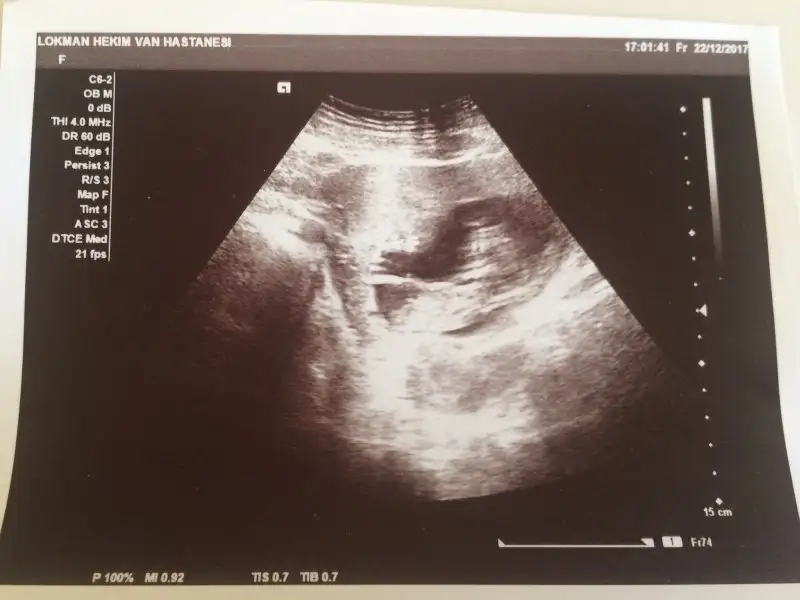

IMG-20180103-WA0001.webp bu ne sence 10 haftalik tam